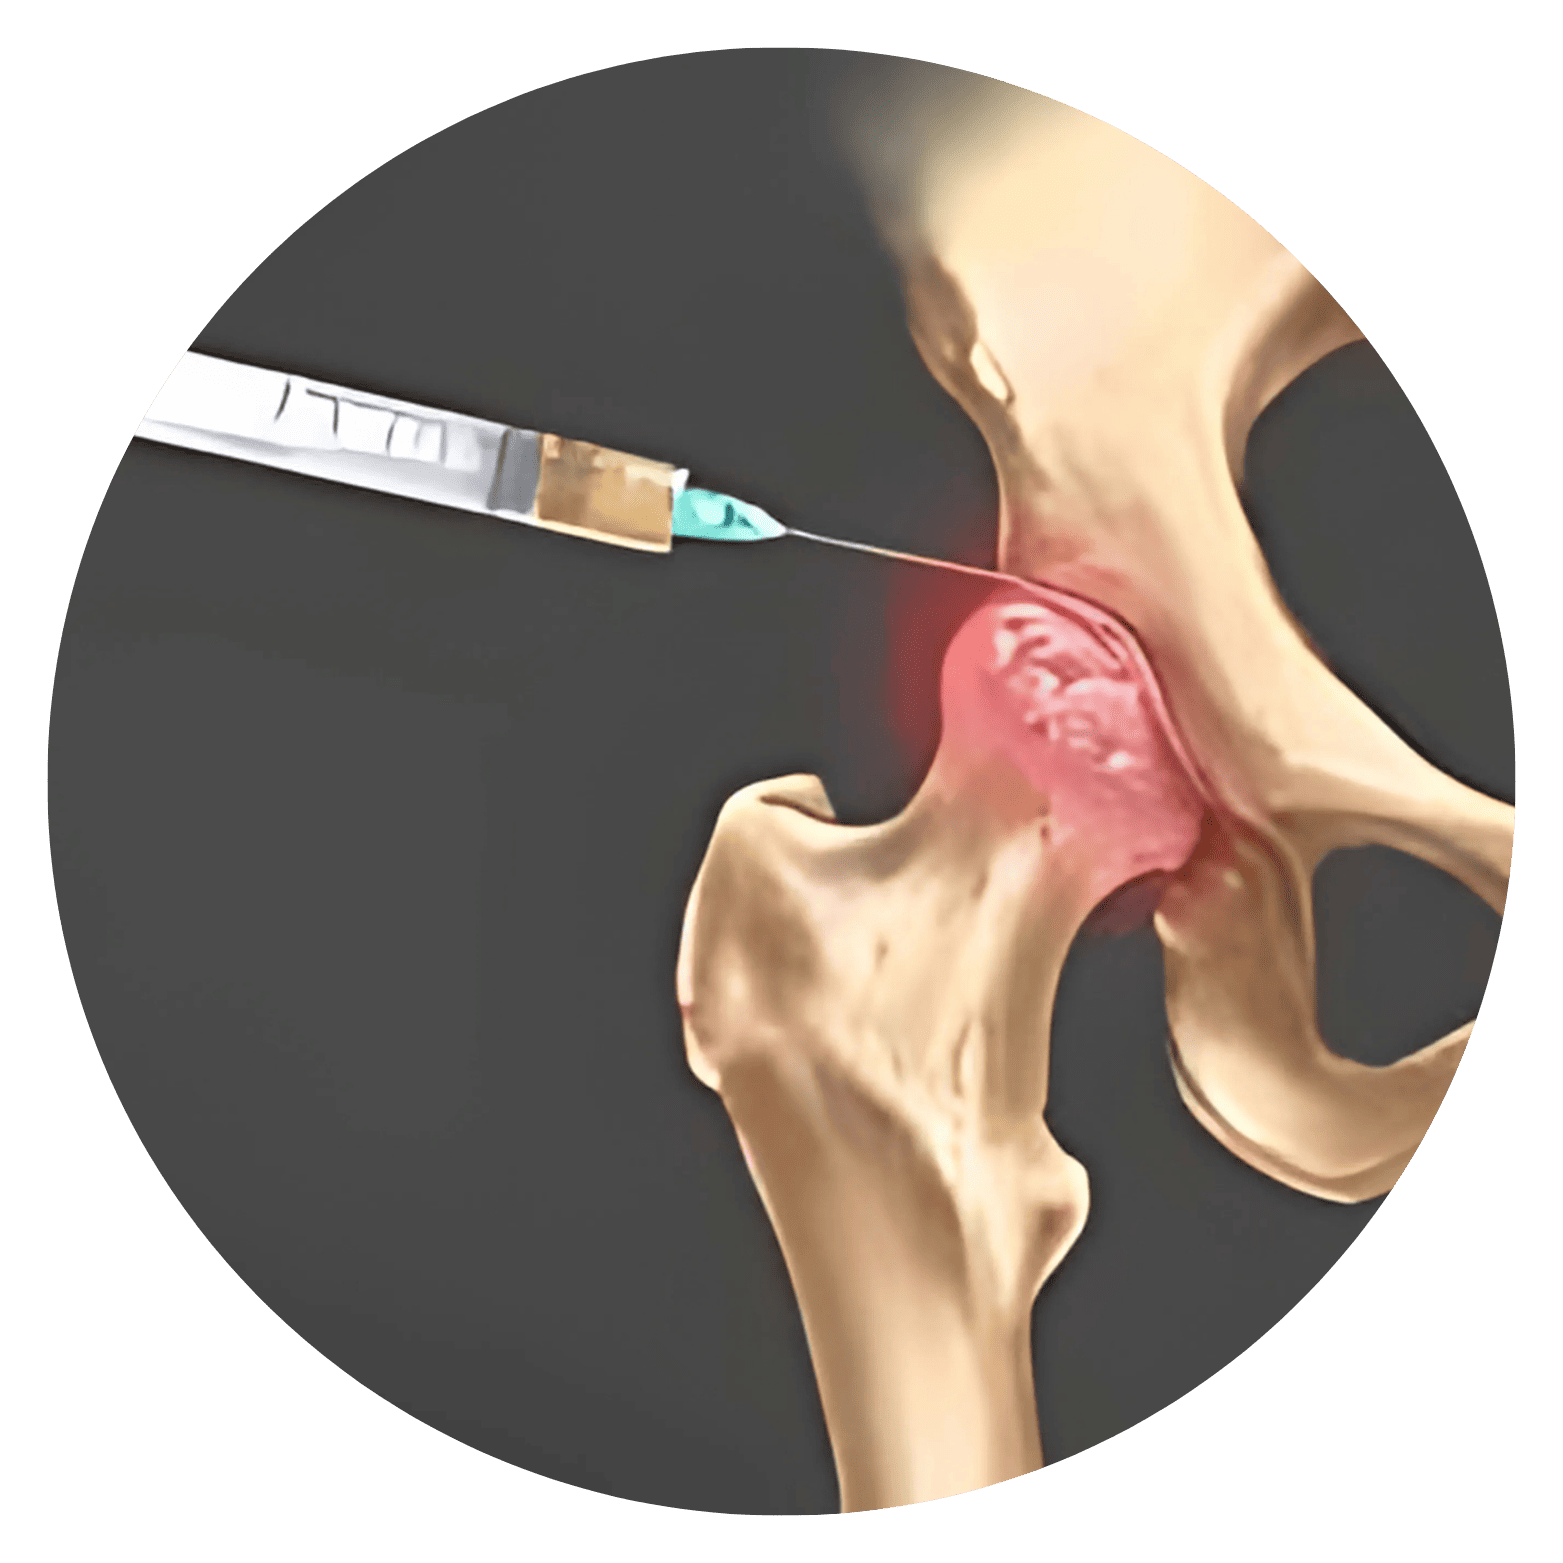

Hérnia de Disco Lombar Aquela dor insuportável na região lombar que impede o simples ato de amarrar os sapatos, ou uma pontada aguda que desce